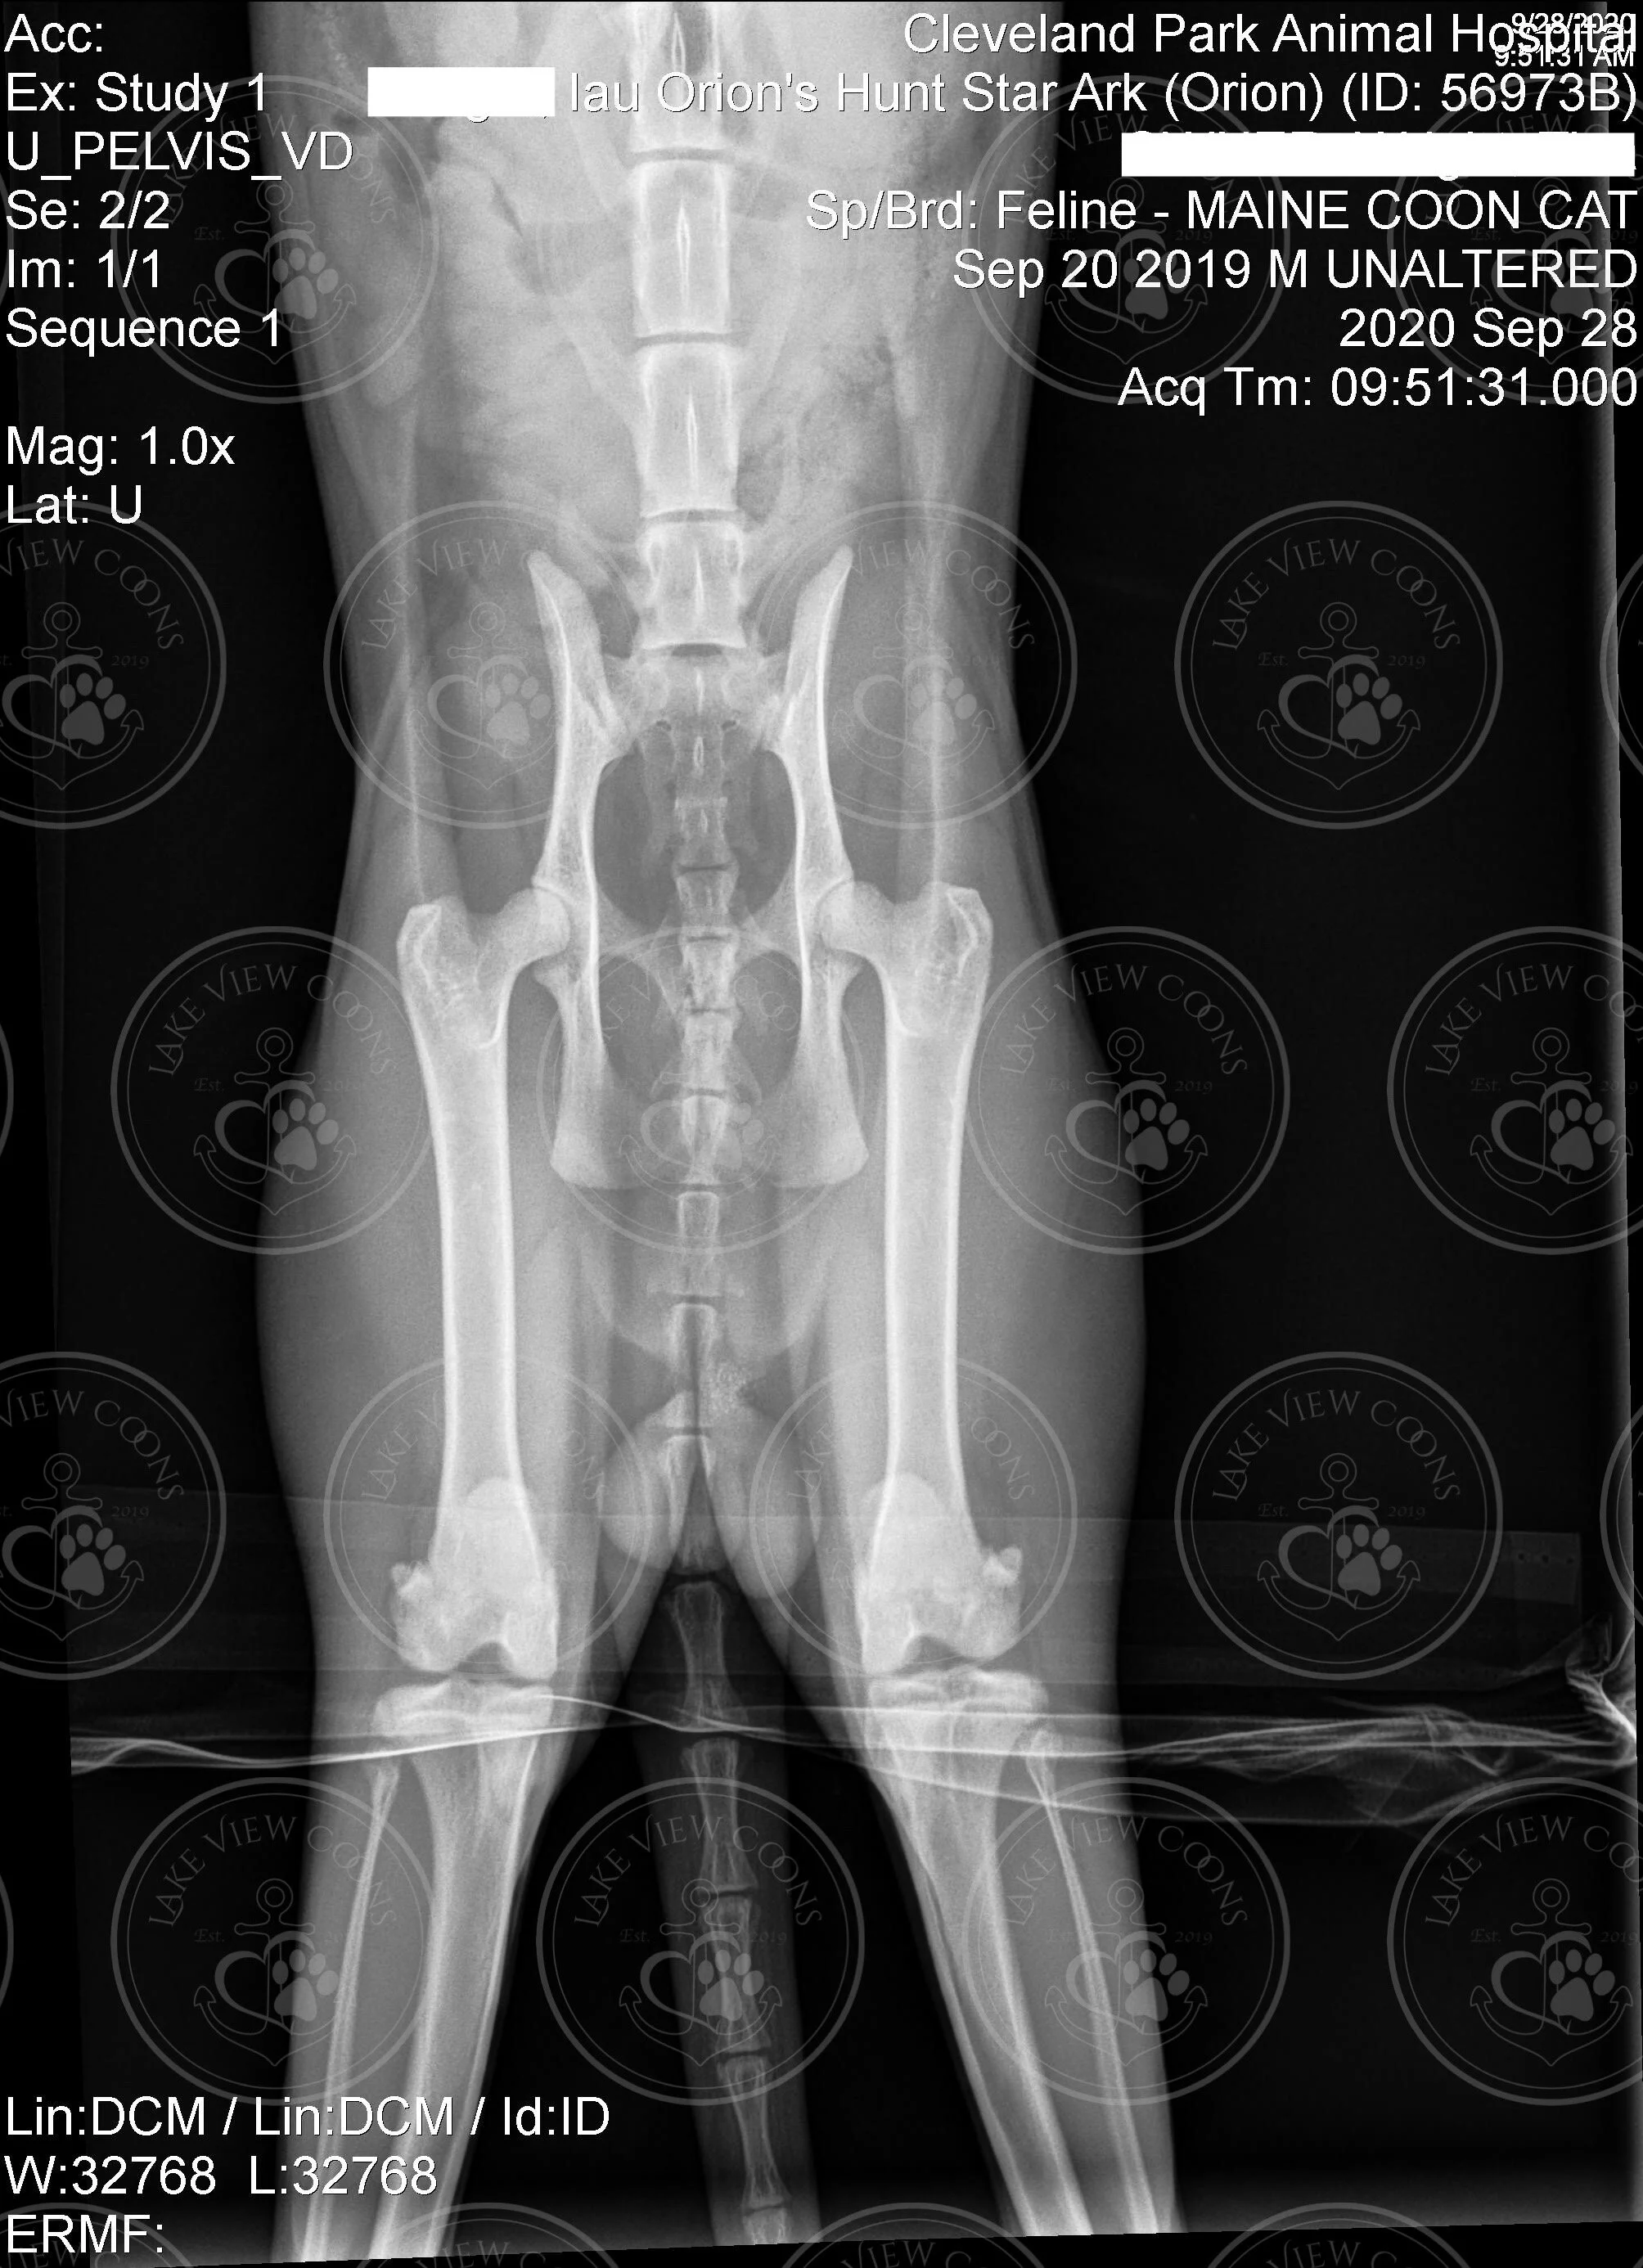

StarArk IAU Orion’s Hunt of Lake View Coons

Heart Echo & Hip X-Ray Results